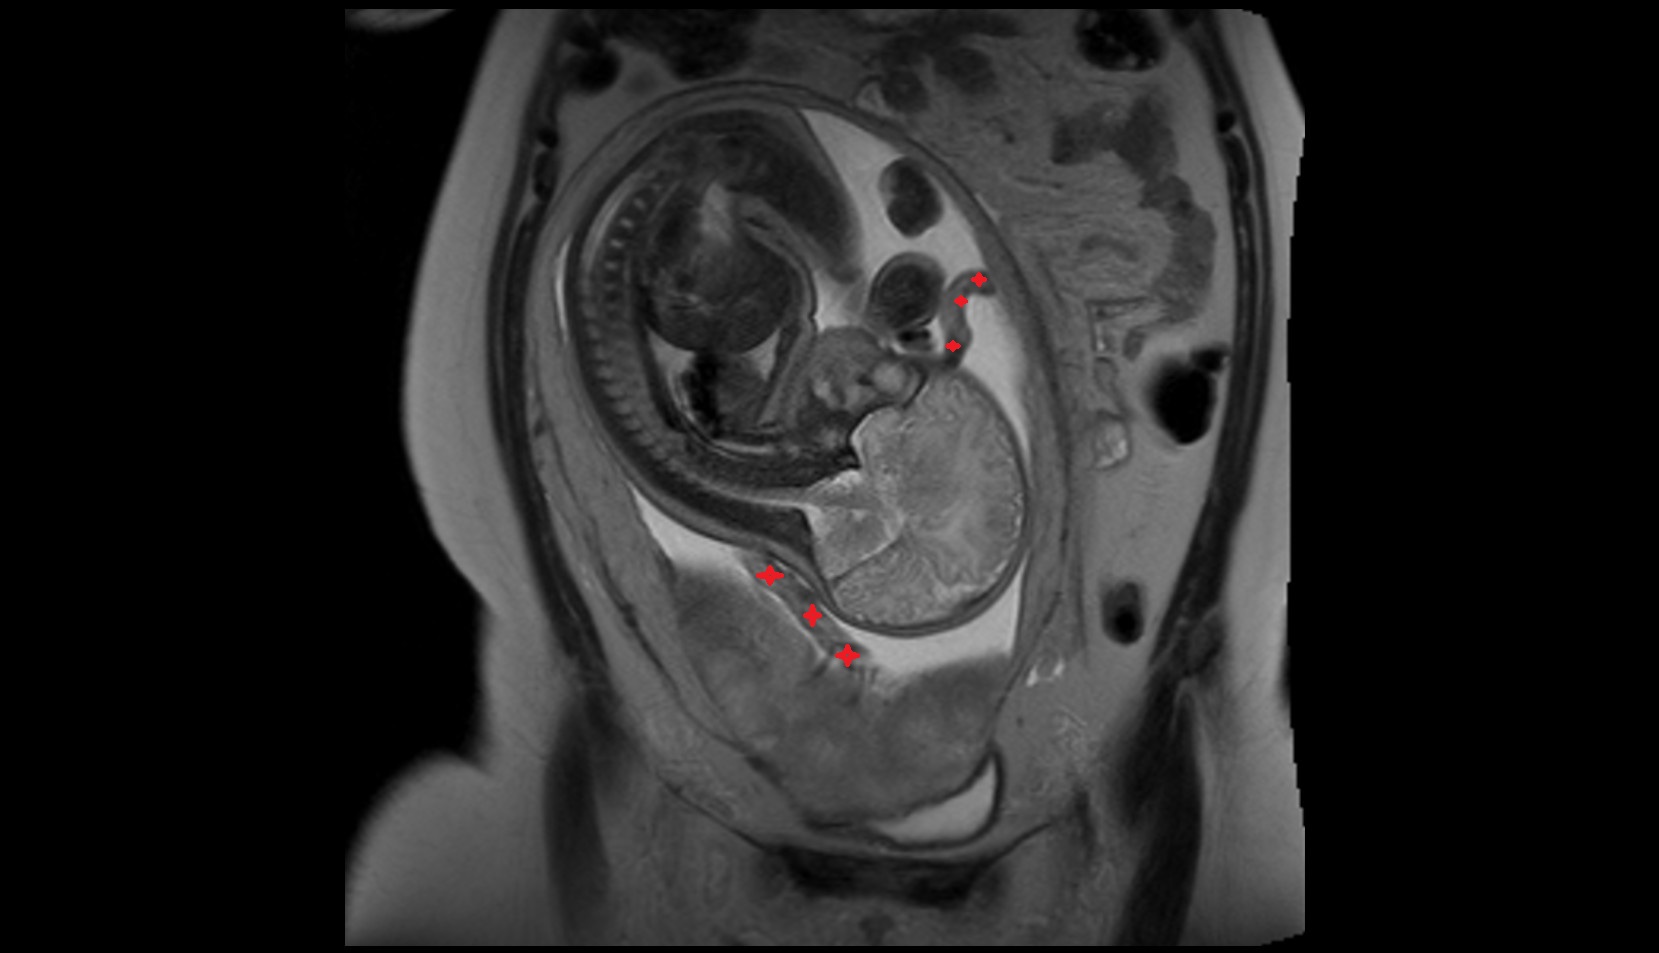

- Placenta

- Uterus (pregnancy)

- Amniotic fluid

- Umbilical cord

- Urinary Bladder in Pregnancy

- Cervix in Pregnancy

- Vagina in Pregnancy

- Fundus of uterus in pregnancy

- Fetal brain

- Fetal cerebellum